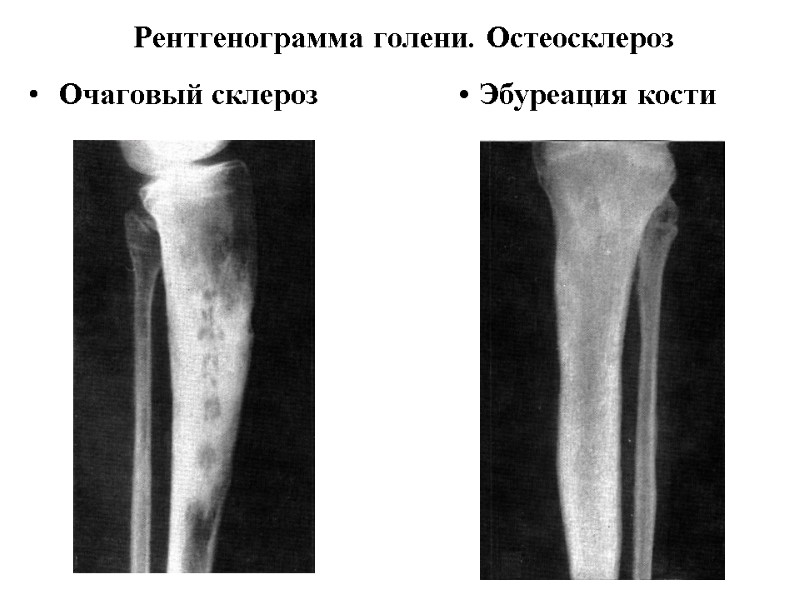

Рентгенограмма голени. Остеосклероз Очаговый склероз • Эбуреация кости